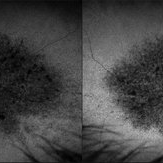

Retinal Aneurysms

Retinal Aneurysms

Aug 6 2025 by Korey Starkey

54 year-old patient presents with scattered peripheral aneurysms with exudates. FA was performed showing peripheral nonperfusion and aneurysms. Treated patient with PRP and focal laser to aneurysms and continued observation.

Photographer: Kore Starkey

Imaging device: Optos

Condition/keywords: aneurysm, branch retinal vein occlusion (BRVO), chorioretinal scar, circinate ring, exudates, fundus photography, lesion, Optos, retinal aneurysms